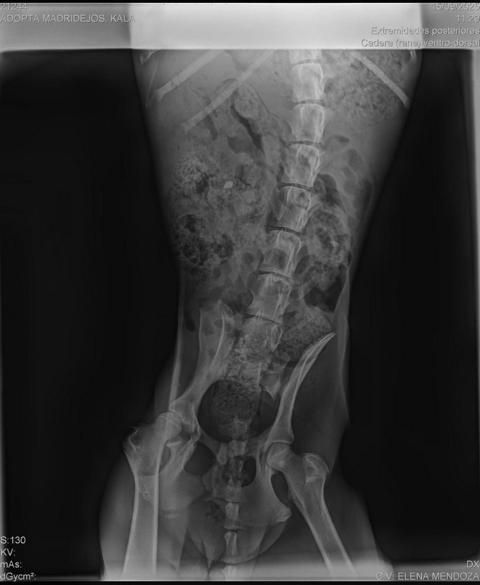

Wir fanden sie allein, viel zu dünn auf einem Feld. Ihr kleiner Körper wirkte schwach, ihr Blick erschöpft… doch das Schlimmste trug sie in sich: eine alte Fraktur an der Hüfte, falsch zusammengewachsen, die ihr ständige Schmerzen bereitete. Niemand hatte ihr damals geholfen. Niemand hatte sich darum gekümmert, sie zu heilen. Und trotzdem kämpfte Kala weiter, überlebte tapfer.

Als wir sie zum Tierarzt brachten, war klar: ihre einzige Chance war eine komplizierte und teure Operation. Ein Eingriff, den wir nicht aufschieben konnten – jeder weitere Tag hätte nur noch mehr Leiden bedeutet. Wir entschieden uns sofort, sie operieren zu lassen. Es gab keine andere Wahl: wir konnten sie nicht zu einem Leben voller Schmerz verurteilen.

Die Operation verlief erfolgreich. Dank dessen hat Kala nun die Möglichkeit, wieder zu laufen und endlich das zu sein, was sie von Anfang an hätte sein sollen: ein glücklicher Welpe. Doch dieses kleine Wunder hat seinen Preis: die Rechnung beträgt 960 €, eine Summe, die wir dringend begleichen müssen, um weiterhin Hunde wie sie retten und versorgen zu können.